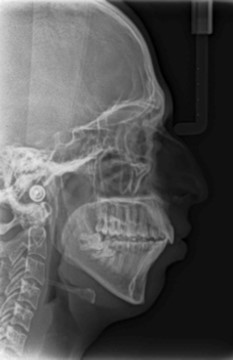

Cephalometric analysis revealed a skeletal Class II pattern, with an orthognathic maxilla and retrognathic mandible with high mandibular plane angle and severely proclined maxillary and mandibular incisors with increased lower anterior facial height. (Figure 3).

Figure 3.Pre-treatment lateral cephalometric radiograph

Pre-treatment lateral cephalometric radiograph

Post treatment lateral cephalometric radiograph was taken to assess the treatment changes. (Figure 9). The changes in maxilla in the anteroposterior direction was insignificant, however an increase in the length of the mandible measured from Condylion (Co) to Gnathion (Gn) and an increase in anterior facial height was observed. Maxillary incisors were retracted dramatically by 8mm and the mandibular incisors were proclined by 3mm to camouflage the skeletal class II malocclusion.(Table 1). Effective expansion of the maxillary constriction as an end-of treatment goal was achieved. (Figure 10a,Figure 10b).